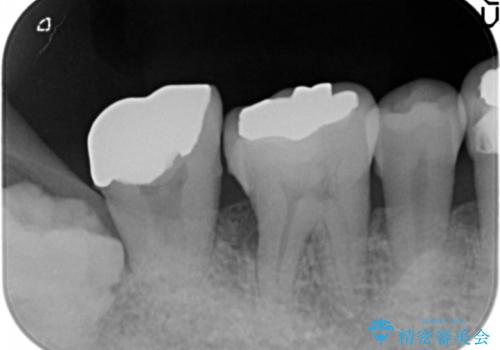

骨を再生させて歯周病を治す 再生療法 50代男性

- 全顎的な重度歯周病の患者様です。

骨吸収の進行している右下臼歯部に、再生療法(骨を増やす手術))を行いました。

再生療法から1年後、リエントリー手術により骨の再生を確認し、骨外科処置(骨を平らにして歯周ポケットの根本的な改善を図る処置)を行いました。

再生療法と骨外科処置により、歯周ポケットは全周2mm以下となりました。